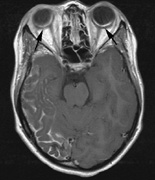

NEUROLOGIC FINDINGS.

- Schwannomas most commonly affect the fifth cranial nerve (CN), but

any cranial nerve may be affected. In contrast to vestibular

schwannomas (CN VIII), these typically do not grow large.84,90 Vestibular schwannomas (acoustic neuromas) are the classic finding

in NF2 (Fig. 7). The risk for malignant transformation is low, but may be higher

with radiation exposure.84,94

- Other tumors: low-grade ependymomas and gliomas may affect the cervical

spine and Brainstem (Fig. 7).84